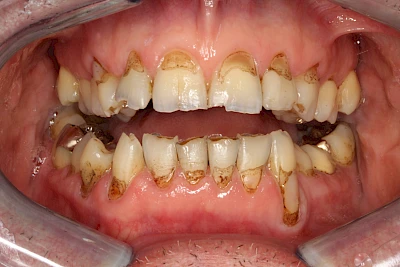

Gerade bei Kindern und Jugendlichen werden zunehmend häufiger bräunliche Verfärbungen mitunter auch mit Formveränderungen (die Oberfläche ist rauh oder zerklüftet) der Zähne beobachtet. Meist sind Schneidezähne oder Backenzähne betroffen. Dies könnte ein Hinweis auf sogenannte Kreidezähne (MIH: Molaren-Inzisiven-Hypomineralisation) sein.

Bräunliche Verfärbung